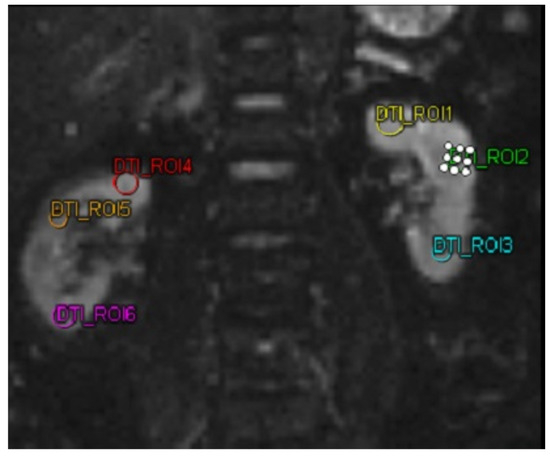

The biomarkers MMP-9 and ICAM-1 were quantified utilizing a sandwich enzyme-linked immunosorbent assay (ELISA) kit (Reed Biotech Ltd., Wuhan, China). For the DTI MRI imaging analysis, a MAGNETOM Vida MRI scanner (Siemens, Erlangen, Germany) was utilized in this study. DTI MRI examination was performed on both kidneys of the subject. Then the subject was subjected to 3 ROIs in each kidney. The three ROIs in each kidney were selected to represent the kidney’s upper, middle, and lower poles, respectively. These ROIs were chosen by a single highly trained technician under the supervision of a senior radiologist. The technician was unaware of the ROI selection results before the intervention when selecting the ROIs for the DTI MRI after the intervention, ensuring unbiased selection. After obtaining the FA value. In this study, FA was taken, with a decrease and increase in FA in patients.

Table 2 shows the analysis of FA, MMP-9, and ICAM-1. In DTI MRI measurements (FA) before and after transfer of autologous dendritic cells (Figure 2), the median value before transfer was 242.57 ± 63.97. After transfer of autologous dendritic cells, the median increased to 305.61 ± 152.32. Statistical tests showed a significant difference with a p-value = 0.042. Figure 3a shows box and whisker FA on DTI MRI.

Figure 2.

MRI DTI examination on a patient using 6 different region of interests. Abbreviations: MRI-DTI: Magnetic Resonance Imaging-Diffusion Tensor Imaging.